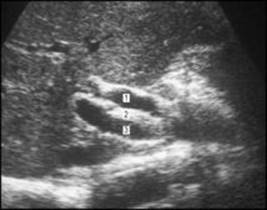

The gallbladder and biliary ducts can be demonstrated by ultrasound (Fig. 5.36), and this technique has largely replaced the visualization of these structures by radiography after the administration of radio-opaque substances which are excreted by the liver into bile. Under direct vision through an endoscope, a catheter can be inserted into the hepatopancreatic ampulla and radio-opaque contrast medium injected, resulting in the radiographic delineation of the bile and pancreatic ducts (endoscopic retrograde cholangiopancreatography). These ducts can now also be demonstrated by the non-invasive technique of magnetic resonance imaging (Fig. 5.37).

Figure 5.36

Ultrasound image of normal structures at porta hepatis: 1, common bile duct; 2, hepatic artery; 3, portal vein.

Provided by Dr D. J. Lomas, Addenbrooke's Hospital, Cambridge.